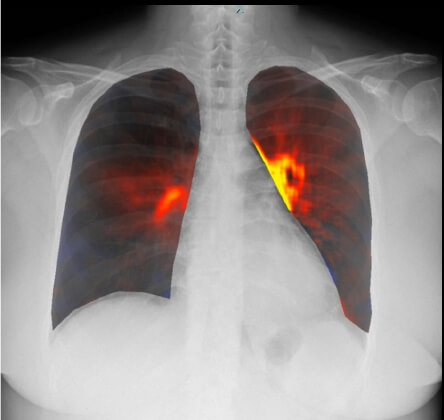

妊娠中に急性肺血栓塞栓症を発症した症例

治療後